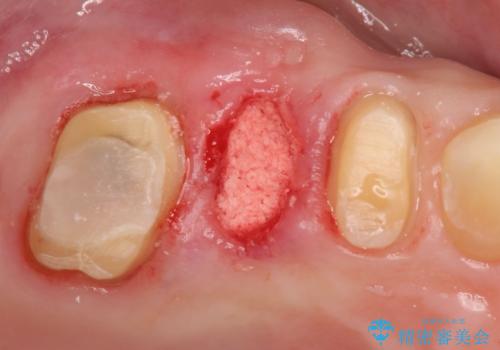

かぶせ(以下クラウン)を外してみたところ、神経のない支台となる歯が折れてしまい抜歯を余儀なくされる状況でした。

抜去後の機能回復方法としてインプラント、入れ歯以外の方法を希望されたためブリッジでの咬合機能回復を行っていくこととなりました。